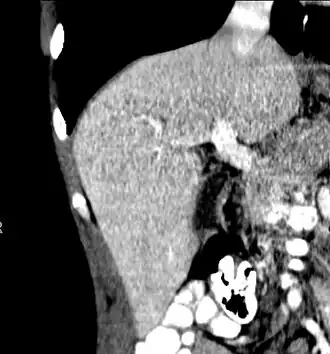

With the recent advances of noninvasive imaging, living liver donors usually have to undergo imaging examinations for liver anatomy to decide if the anatomy is feasible for donation. The evaluation is usually performed by multidetector row computed tomography (MDCT) and magnetic resonance imaging (MRI). MDCT is good in vascular anatomy and volumetry. MRI is used for biliary tree anatomy. Donors with very unusual vascular anatomy, which makes them unsuitable for donation, could be screened out to avoid unnecessary operations.

-

MDCT image. Arterial anatomy contraindicated for liver donation -

MDCT image. Portal venous anatomy contraindicated for liver donation -

MDCT image. 3D image created by MDCT can clearly visualize the liver, measure the liver volume, and plan the dissection plane to facilitate the liver transplantation procedure. -

Phase contrast CT image. Contrast is perfusing the right liver but not the left due to a left portal vein thrombus.